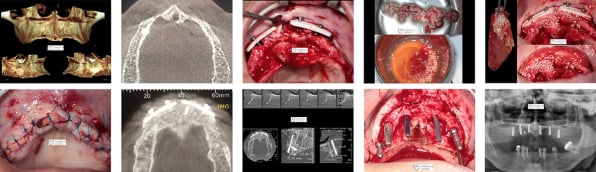

Os produtos OSTEOSYNT vêm sendo cada vez mais utilizados na Implantodontia, nos procedimentos de reconstrução do rebordo alveolar total ou parcialmente perdido, como conseqüência de doenças periodontais, cistos, tumores, traumatismos e consequente perda de elementos e necessidade de sua substituição.

Veja abaixo alguns casos já tratados com as biossoluções EincoBio com resultados de sucesso:

- Reconstrução alveolar de vários elementos;

- Aumento de rebordo vertical e horizontal;